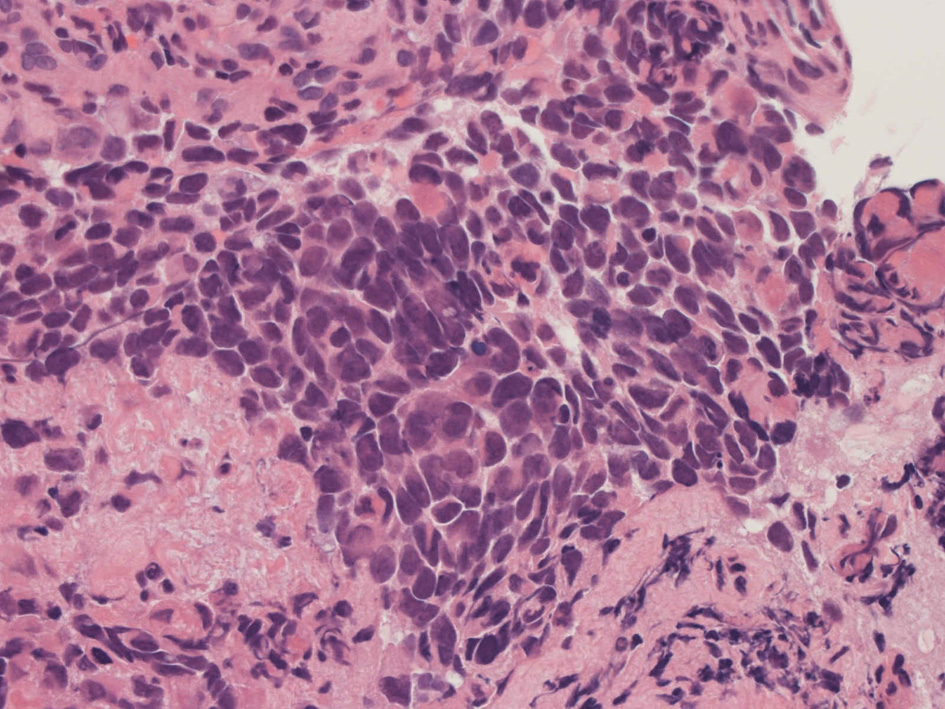

Alveolar rhabdomyosarcoma

Alveolar rhabdomyosaroma

Undifferentiated small round cell tumors of the sinonasal tract

rhabdomyosarcoma 横紋筋肉腫

40歳女性 鼻粘膜腫瘤

右頸部のしこりを自覚。近医MRIで頸部多発リンパ節腫大あり当院を紹介される。右顎下, 右鎖骨上窩にも多数のリンパ節を触れる。穿刺細胞診ではcarcinoma疑い。右鼻腔, 上顎洞にも腫瘤が認められリンパ節腫大との関係を調べるために鼻腔腫瘤の生検が行われる。

病理組織所見

small round cell tumorの中でrhabdomyosarcomaは腫瘍細胞に種々の抗原が陽性となるため診断を誤ることがあり注意が必要である*1

*1 Bahrami A, et al., Aberrant expression of epithelial and neuroendocrine markers in alveolar rhabdomyosarcoma: a potentially serious diagnostic pitfall. Mod Pathol. 2008 Jul;21(7):795-806. Epub 2008 May 16. PMID:1848799199